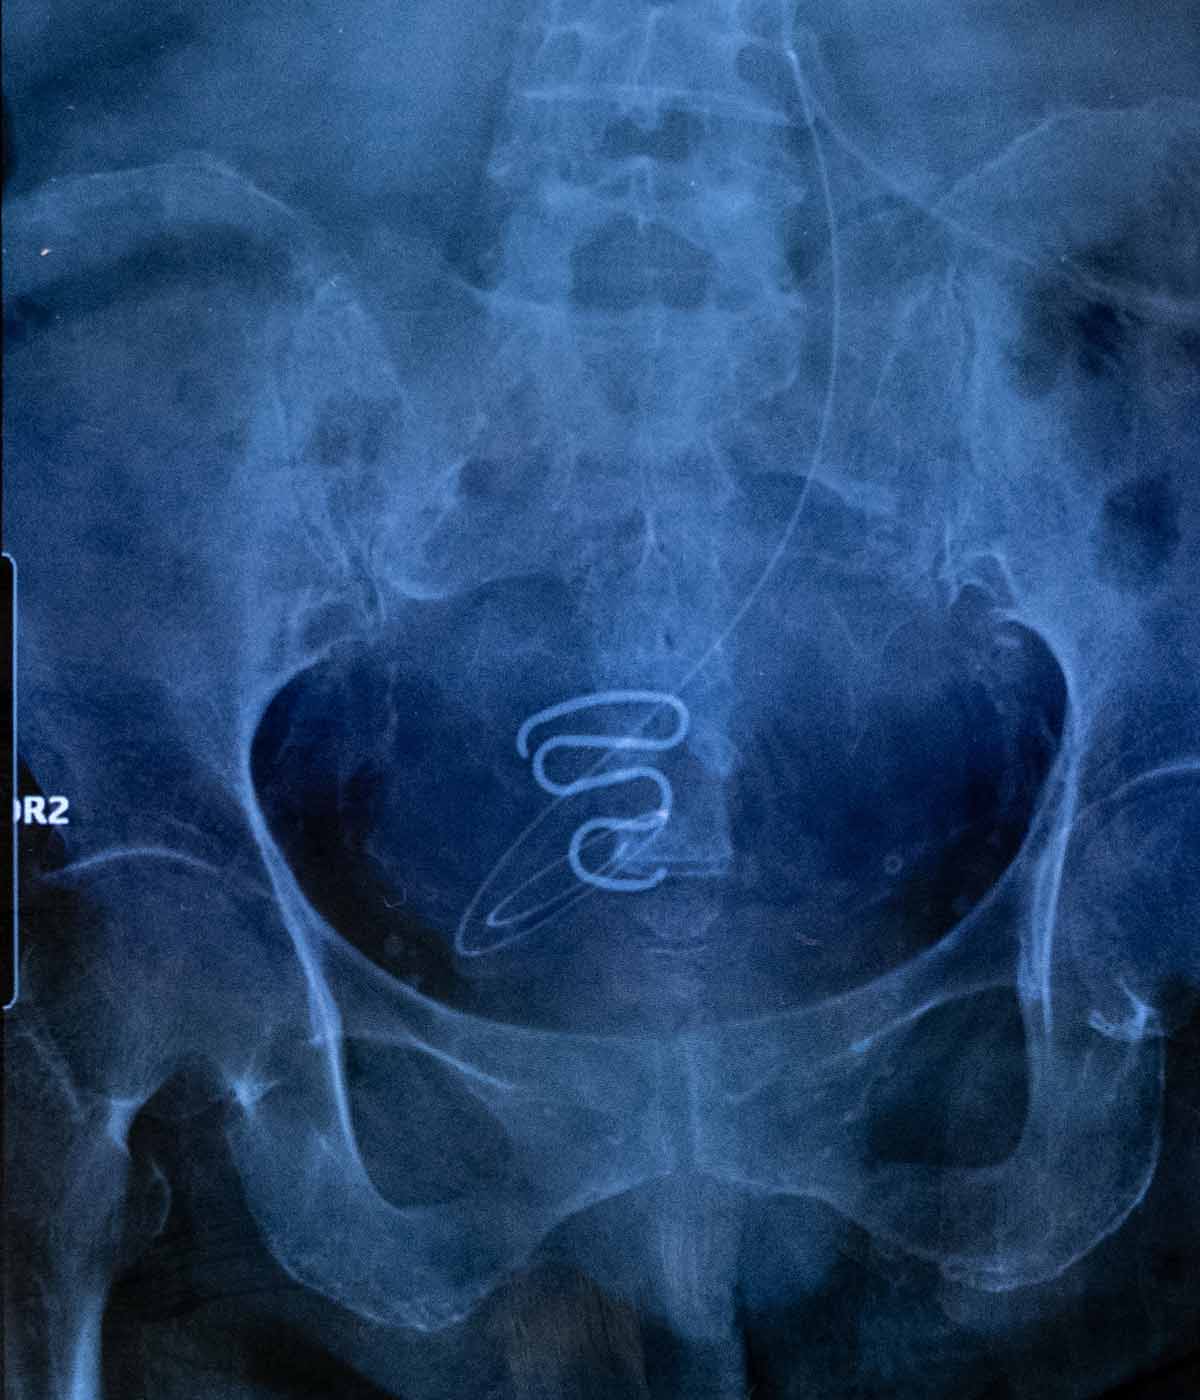

¿Pero esas fotos por sí solas cuentan algo?, se debate en la mesa mientras en el escenario la fotógrafa Juliette Pavy recoge el premio Photographer of the Year por su magnífico trabajo sobre el programa de contracepción forzada llevado a cabo en Groenlandia hace décadas.

La pregunta es muy pertinente, pero lo cierto es que los delicados retratos y las imágenes que componen la narrativa del reportaje Spiralkampagnen -en referencia a la espiral usada como método anticonceptivo forzoso en mujeres inuit- le han valido a la francesa el máximo galardón de esta edición de los premios, así como el primer premio en la categoría de Proyectos de Documentación.

Imágenes que rehuyen de la inmediatez y la actualidad y se centran en un trabajo de largo recorrido dispuesto a desenterrar historias dolorosas y abordar ese trauma colectivo, concendiendo a las víctimas todo el protagonismo.